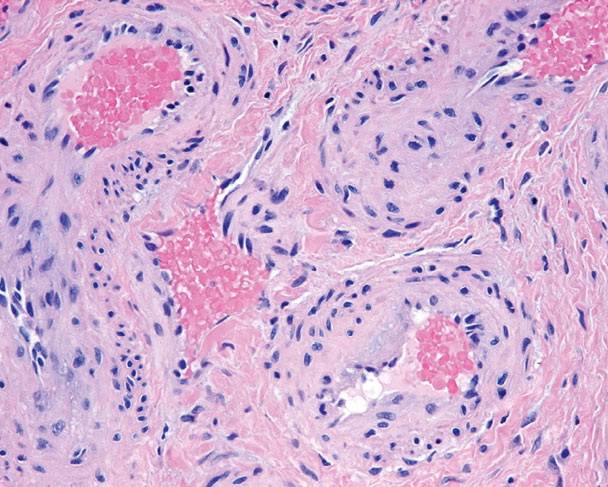

Arteriovenous hemangioma =ورم وعائي شرياني وريدي